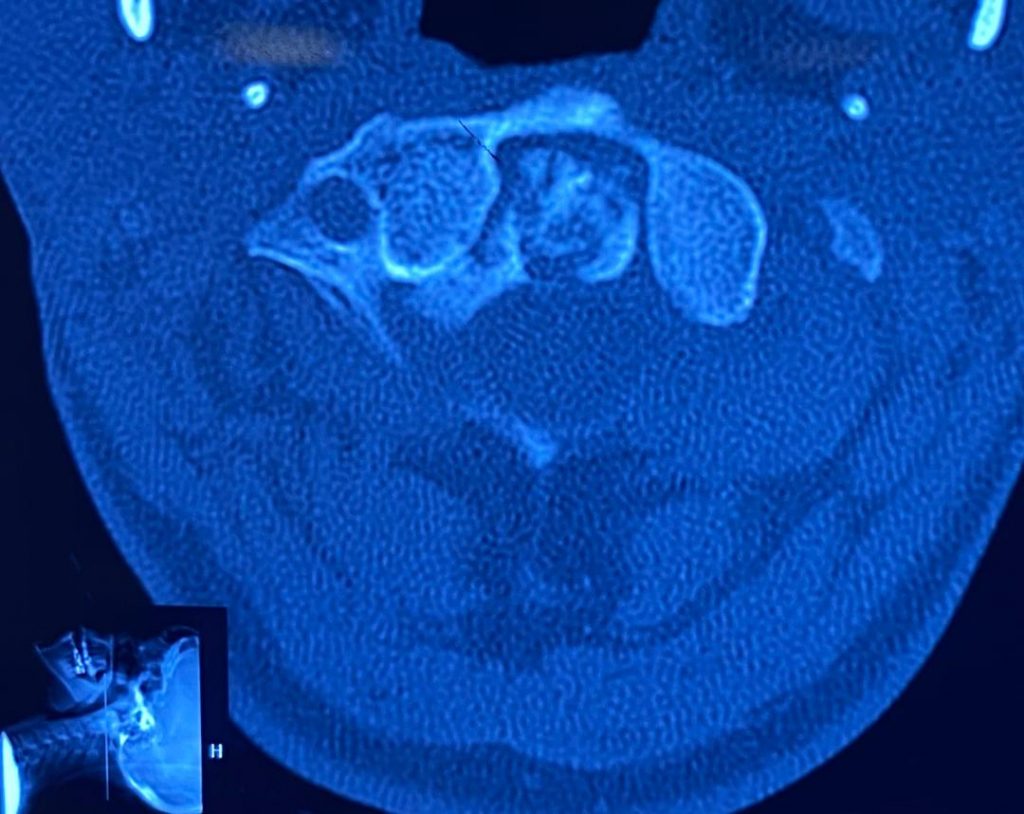

بیمار خانم جوان با سابقه ضربه شدید گردن و شکستگی زائده ادونتویید مهره دوم گردن که تحت عمل جراحی قرار گرفتند. تصاویر قبل و بعد از عمل را در زیر مشاهده می نمایید . همچنین توضیحات دکتر باغبان را در حین جراحی در ویدئوی انتهای مقالات مشاهده کنید. (ویدئو حاوی تصاویر جراحی می باشد)

تصاویر قبل از عمل